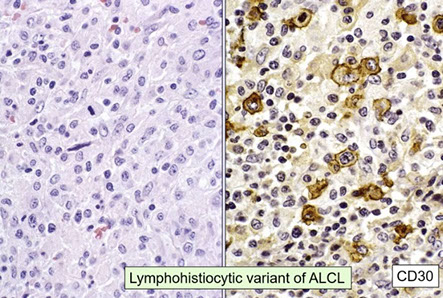

Anaplastic large cell lymphoma (ALCL), ALK positive

Anaplastic large cell lymphoma (ALCL), ALK negative